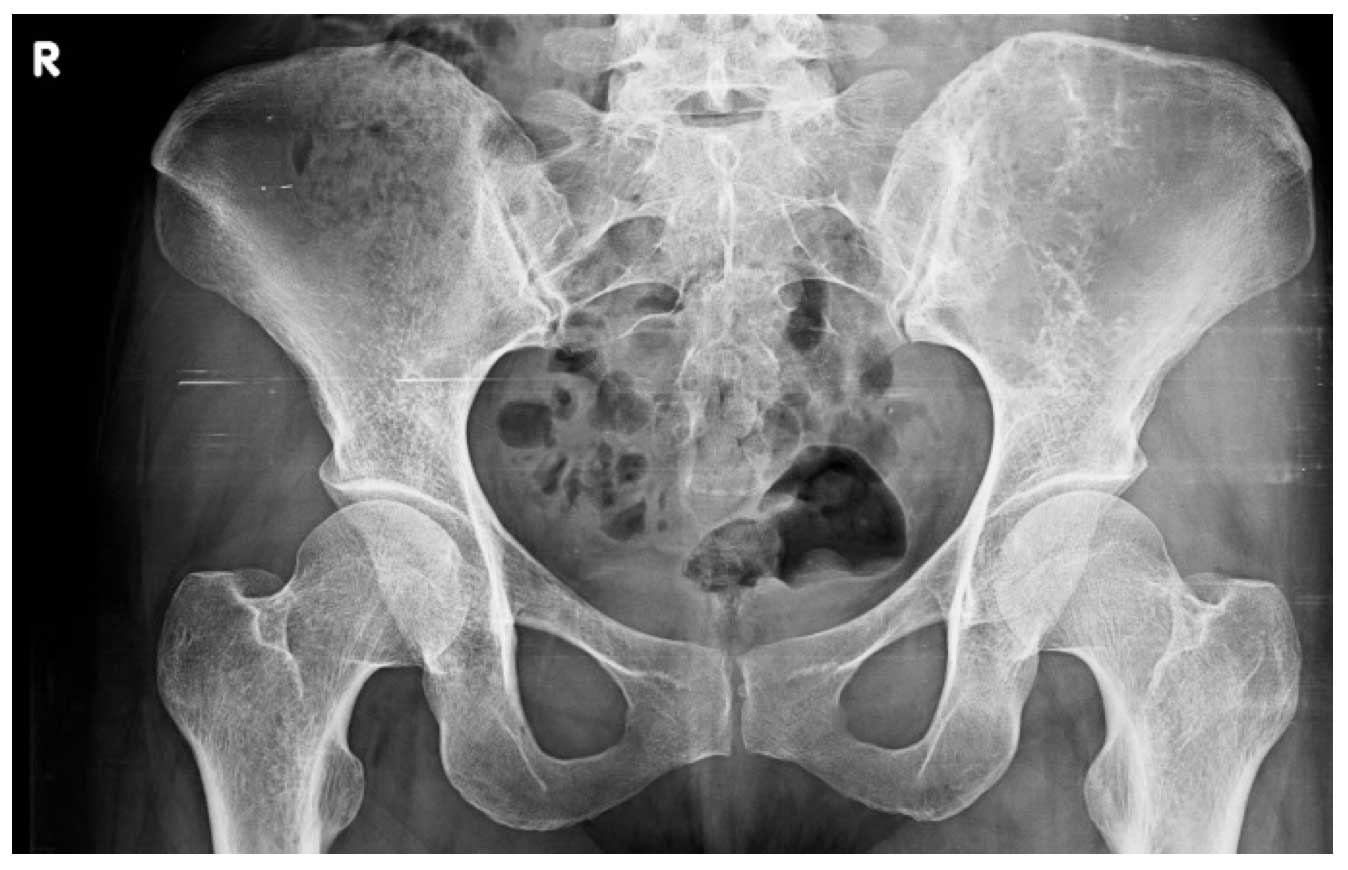

Ameliyat Öncesi: Röntgende sol iliak kanatta yeniklik görülmekte.